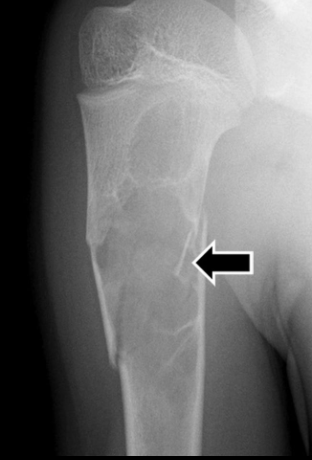

RX

- Lésion lytique

- Bien délimitée

- Géographique

- Pseudo-loculée

- Signe du “fragment tombé / fallen fragment” sur une fracture, le fragment tombe dans la partie lytique

- Centré, contrairement au kyste osseux anévrismal (ABC) qui est excentré

- Rique de fracture pathologique

Fallen fragment sign